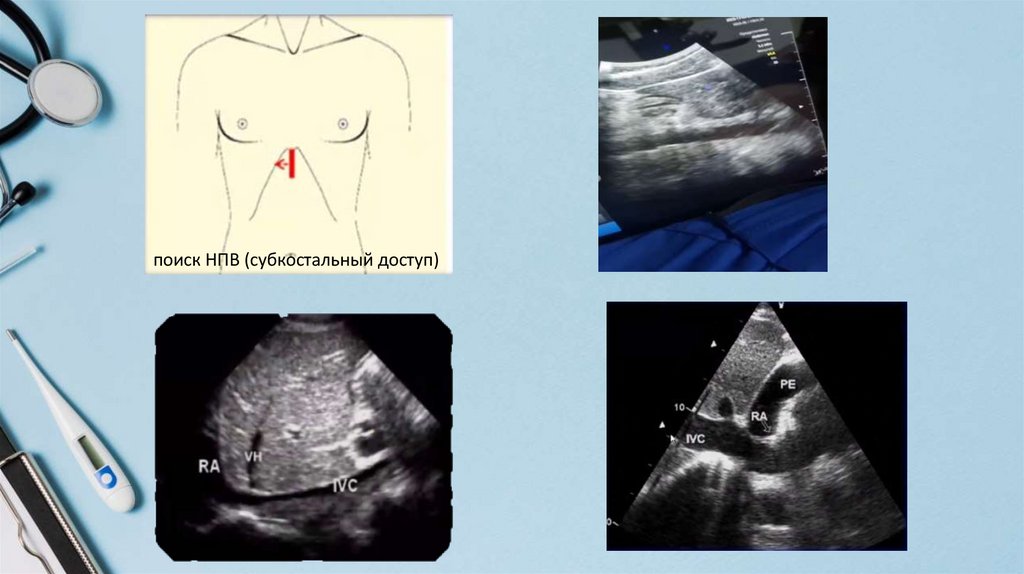

поиск НПВ (субкостальный доступ)

14.